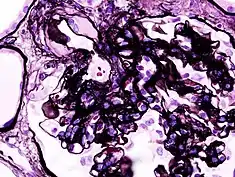

| Microscopic image of diabetic glomerulosclerosis, the main cause of nephrotic syndrome in adults. | |

_PAM.jpg.webp)

Secondary causes of nephrotic syndrome have the same histologic patterns as the primary causes, though they may exhibit some differences suggesting a secondary cause, such as inclusion bodies.[24] They are usually described by the underlying cause, such as: